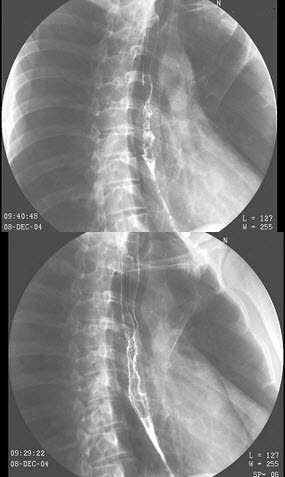

24、单项选择题

女,2岁半,突然哭闹3小时,急性面容,腹部触诊上腹区似可扪及包块,行钡灌肠检查,如图所示,最可能的诊断为()

A.肠套叠

B.先天性巨结肠

C.结肠扭转

D.结肠炎

E.结肠癌